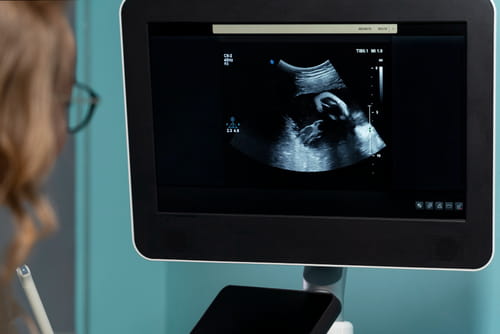

Ecografías del embarazo

Precisión médica y tecnología de avanzada para acompañar cada etapa del embarazo y cuidar lo más importante: tu bebé.